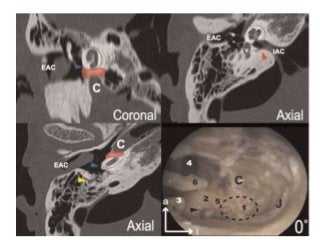

A schematic representation of the

position of the internal audi tory

canal in middle cranial fossa

approach. EAC, external auditory

canal; IAC, internal auditory

canal; SSC, superior semicircular

canal; SPS, superior petrosal

sinus.